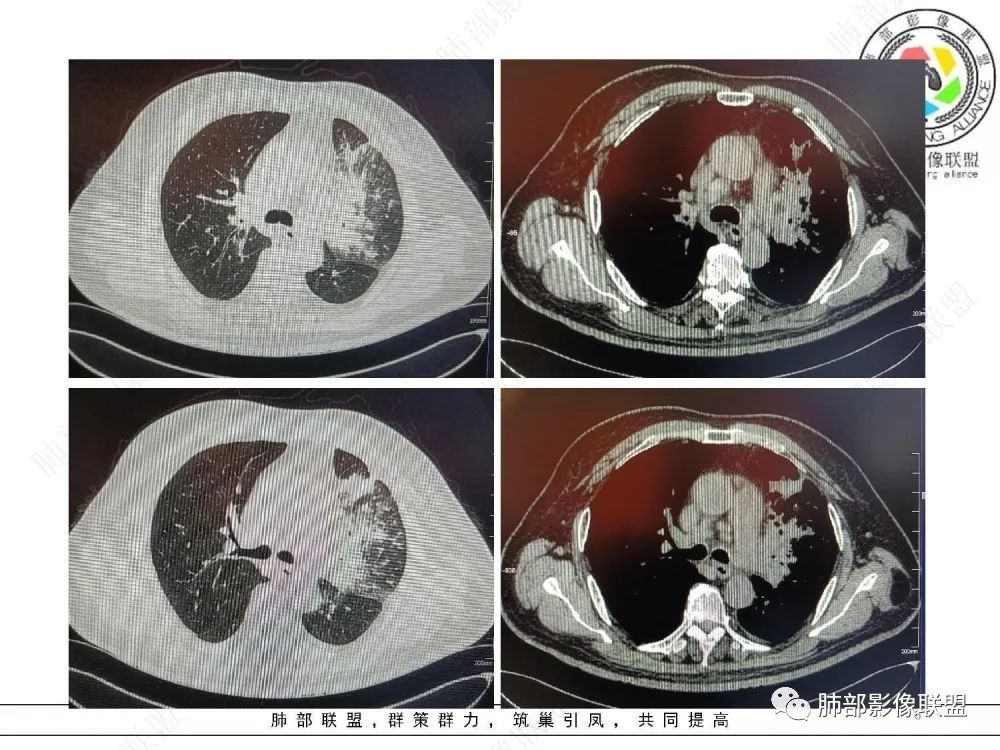

三、影像表现:左肺上叶多发片状高密度影,散在,边缘模糊,支气管壁稍增厚,中轴间质、小叶间隔增厚、有结节感,左肺上叶前段病灶可见胸膜增厚,部分小支气管不能分辨;右肺上叶后段混合磨玻璃结节,边界清,邻近胸膜凹陷;纵膈淋巴结肿大;心包增厚;左侧少量胸水。此外,扫及右侧胸腔内甲状腺肿;左侧肩胛骨旁肌群内脂肪瘤。

四、综合分析:老年男性,以咳嗽咳痰为主要临床表现,无发热,白细胞正常,影像表现为左肺上叶片影,前段结节影、胸膜增厚、部分小支气管不能分辨。左肺上叶中轴间质增厚、小叶间隔增厚、结节感,肺门纵隔见肿大淋巴结,尽管肺部病病灶边缘特征不典型,但高度疑及癌性淋巴管炎这一“次生灾害”却具有相当重要提示意义,而肺癌中最常伴癌淋的就包括腺癌。右肺上叶后段混合磨玻璃结节,边界清楚,张力明显,具有一定特征性,高度指向浸润性腺癌。这对于左肺病灶具有一定程度“助攻”效应。总体而言,本例左肺病灶的诊断关键点在于判断出癌性淋巴管炎。癌性淋巴管炎的结节在外围间质多见,小叶间隔可呈串珠状、结节状增厚,由于出血及水肿,小叶间隔增厚较明显,或呈不规则增厚。有的肺小叶呈多角状阵列。常合并胸水。